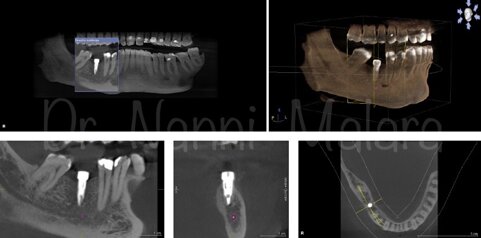

OPT pre operatoriaProgettazione computer guidataOPT post operatpria in seguito all'inserimento degli impianti

Sito d'intervento : edentulia primo molare inf dx (4.6)

Progettazione con software dedicato